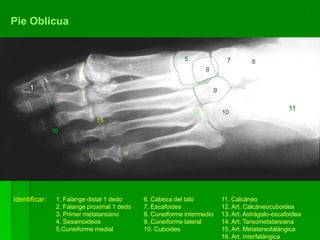

Pie Oblicua

Identificar: 1. Falange distal 1 dedo

2. Falange proximal 1 dedo

3. Primer metatarsiano

4. Sesamoideos

5.Cuneiforme medial

6. Cabeza del talo

7. Escafoides

8. Cuneiforme intermedio

9. Cuneiforme lateral

10. Cuboides

11. Calcáneo

12. Art. Calcáneocuboidea

13. Art. Astrágalo-escafoidea

14. Art. Tarsometatarsiana

15. Art. Metatarsofalángica

16. Art. Interfalángica